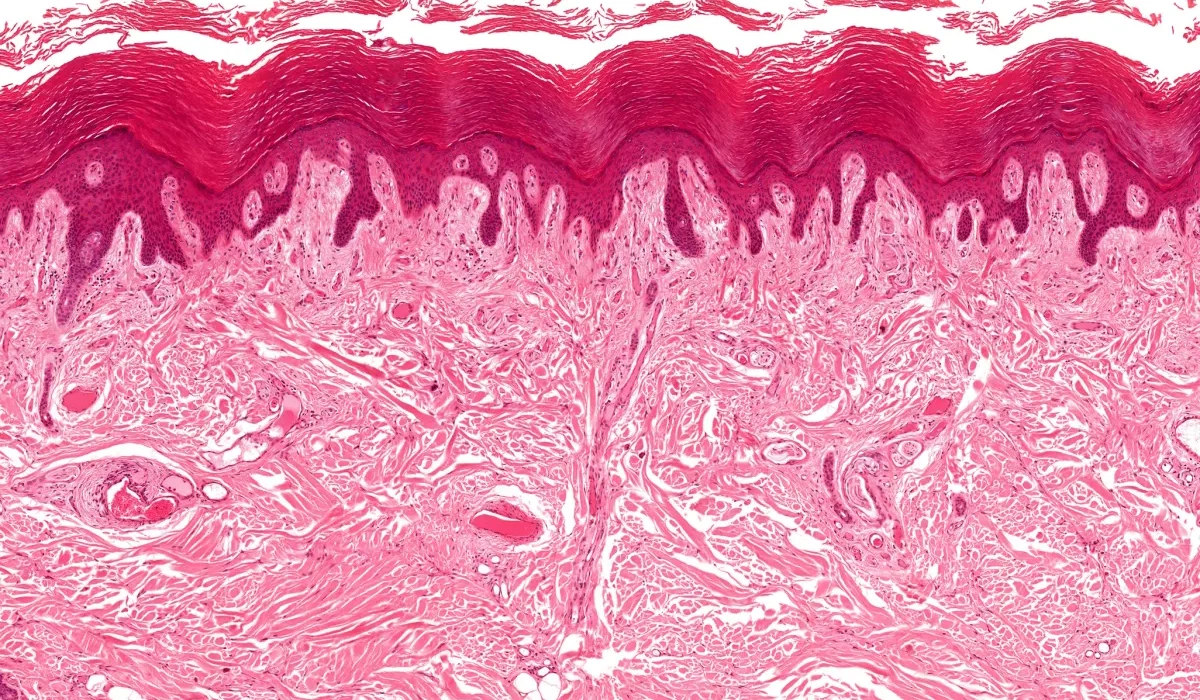

Jusqu’à récemment, les chercheurs pensaient que le tissu conjonctif entourant nos organes formait une couche épaisse et compacte. C’était l’image qu’ils avaient en laboratoire, lorsque les échantillons étaient examinés hors du corps. Cependant, lors d’une **endoscopie**, une petite caméra a révélé une structure inattendue : dans un corps vivant, ce tissu se révélait être un « espace ouvert, rempli de liquide, soutenu par un treillis constitué de gros faisceaux de collagène », a déclaré le pathologiste et auteur de l’étude, **Neil Theise**. Ce réseau de canaux s’étend dans tout le corps et agit comme un coussin souple et élastique, protégeant les organes contre les chocs extérieurs lors des mouvements du corps.

Theise suppose que la méthode de prélèvement utilisée pour réaliser les lames, qui était alors la seule façon d’examiner le tissu en détail, a pu déformer les spécimens. «**Prendre simplement un morceau de tissu dans cet espace** permet au liquide de s’écouler, et les faisceaux de collagène de s’affaisse**r**, à l’image des étages d’un bâtiment en train de s’effondrer. »

Un expert en biotechnologie affirme que “dans la prochaine décennie, la plupart des cancers seront curables”.

Les chercheurs ont remarqué de petites fissures dans le tissu au microscope, mais pensaient que celles-ci étaient dues à une manipulation brutale lors du transfert sur les lames. Cependant, selon Theise, «**il ne s’agissait pas d’artefacts**. Ce sont les résidus des espaces effondrés. Ils étaient présents depuis le début. C’est seulement grâce à l’observation de tissus vivants que nous avons pu les identifier. »

L’interstitium ne se résume pas simplement à l’« espace entre les cellules ». Theise et son équipe estiment qu’il devrait être reclassé en tant qu’organe à part entière, en raison de ses propriétés uniques et de sa structure, qui sont selon lui «**hautement spécifiques et dépendantes des structures et types cellulaires qui le composent**».